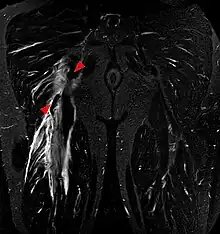

Tear of the hamstrings muscles at the ischial tuberosity seen on MRI (coronal STIR). The arrowheads indicate the tuber and the retracted tendon stump. Significant bleeding around and into the muscles.

Imaging the hamstring muscles is usually performed with an ultrasound and/or MRI.[9]  The biceps femoris is most commonly injured, followed by semitendinosus. Semimembranosus injury is rare. Imaging is useful in differentiating the grade of strain, especially if the muscle is completely torn.[10] In this setting, the level and degree of retraction can be determined, serving as a useful roadmap prior to any surgery. Those with a hamstring strain of greater than 60 mm (2.4 in) in length have a greater risk of recurrence.[11]